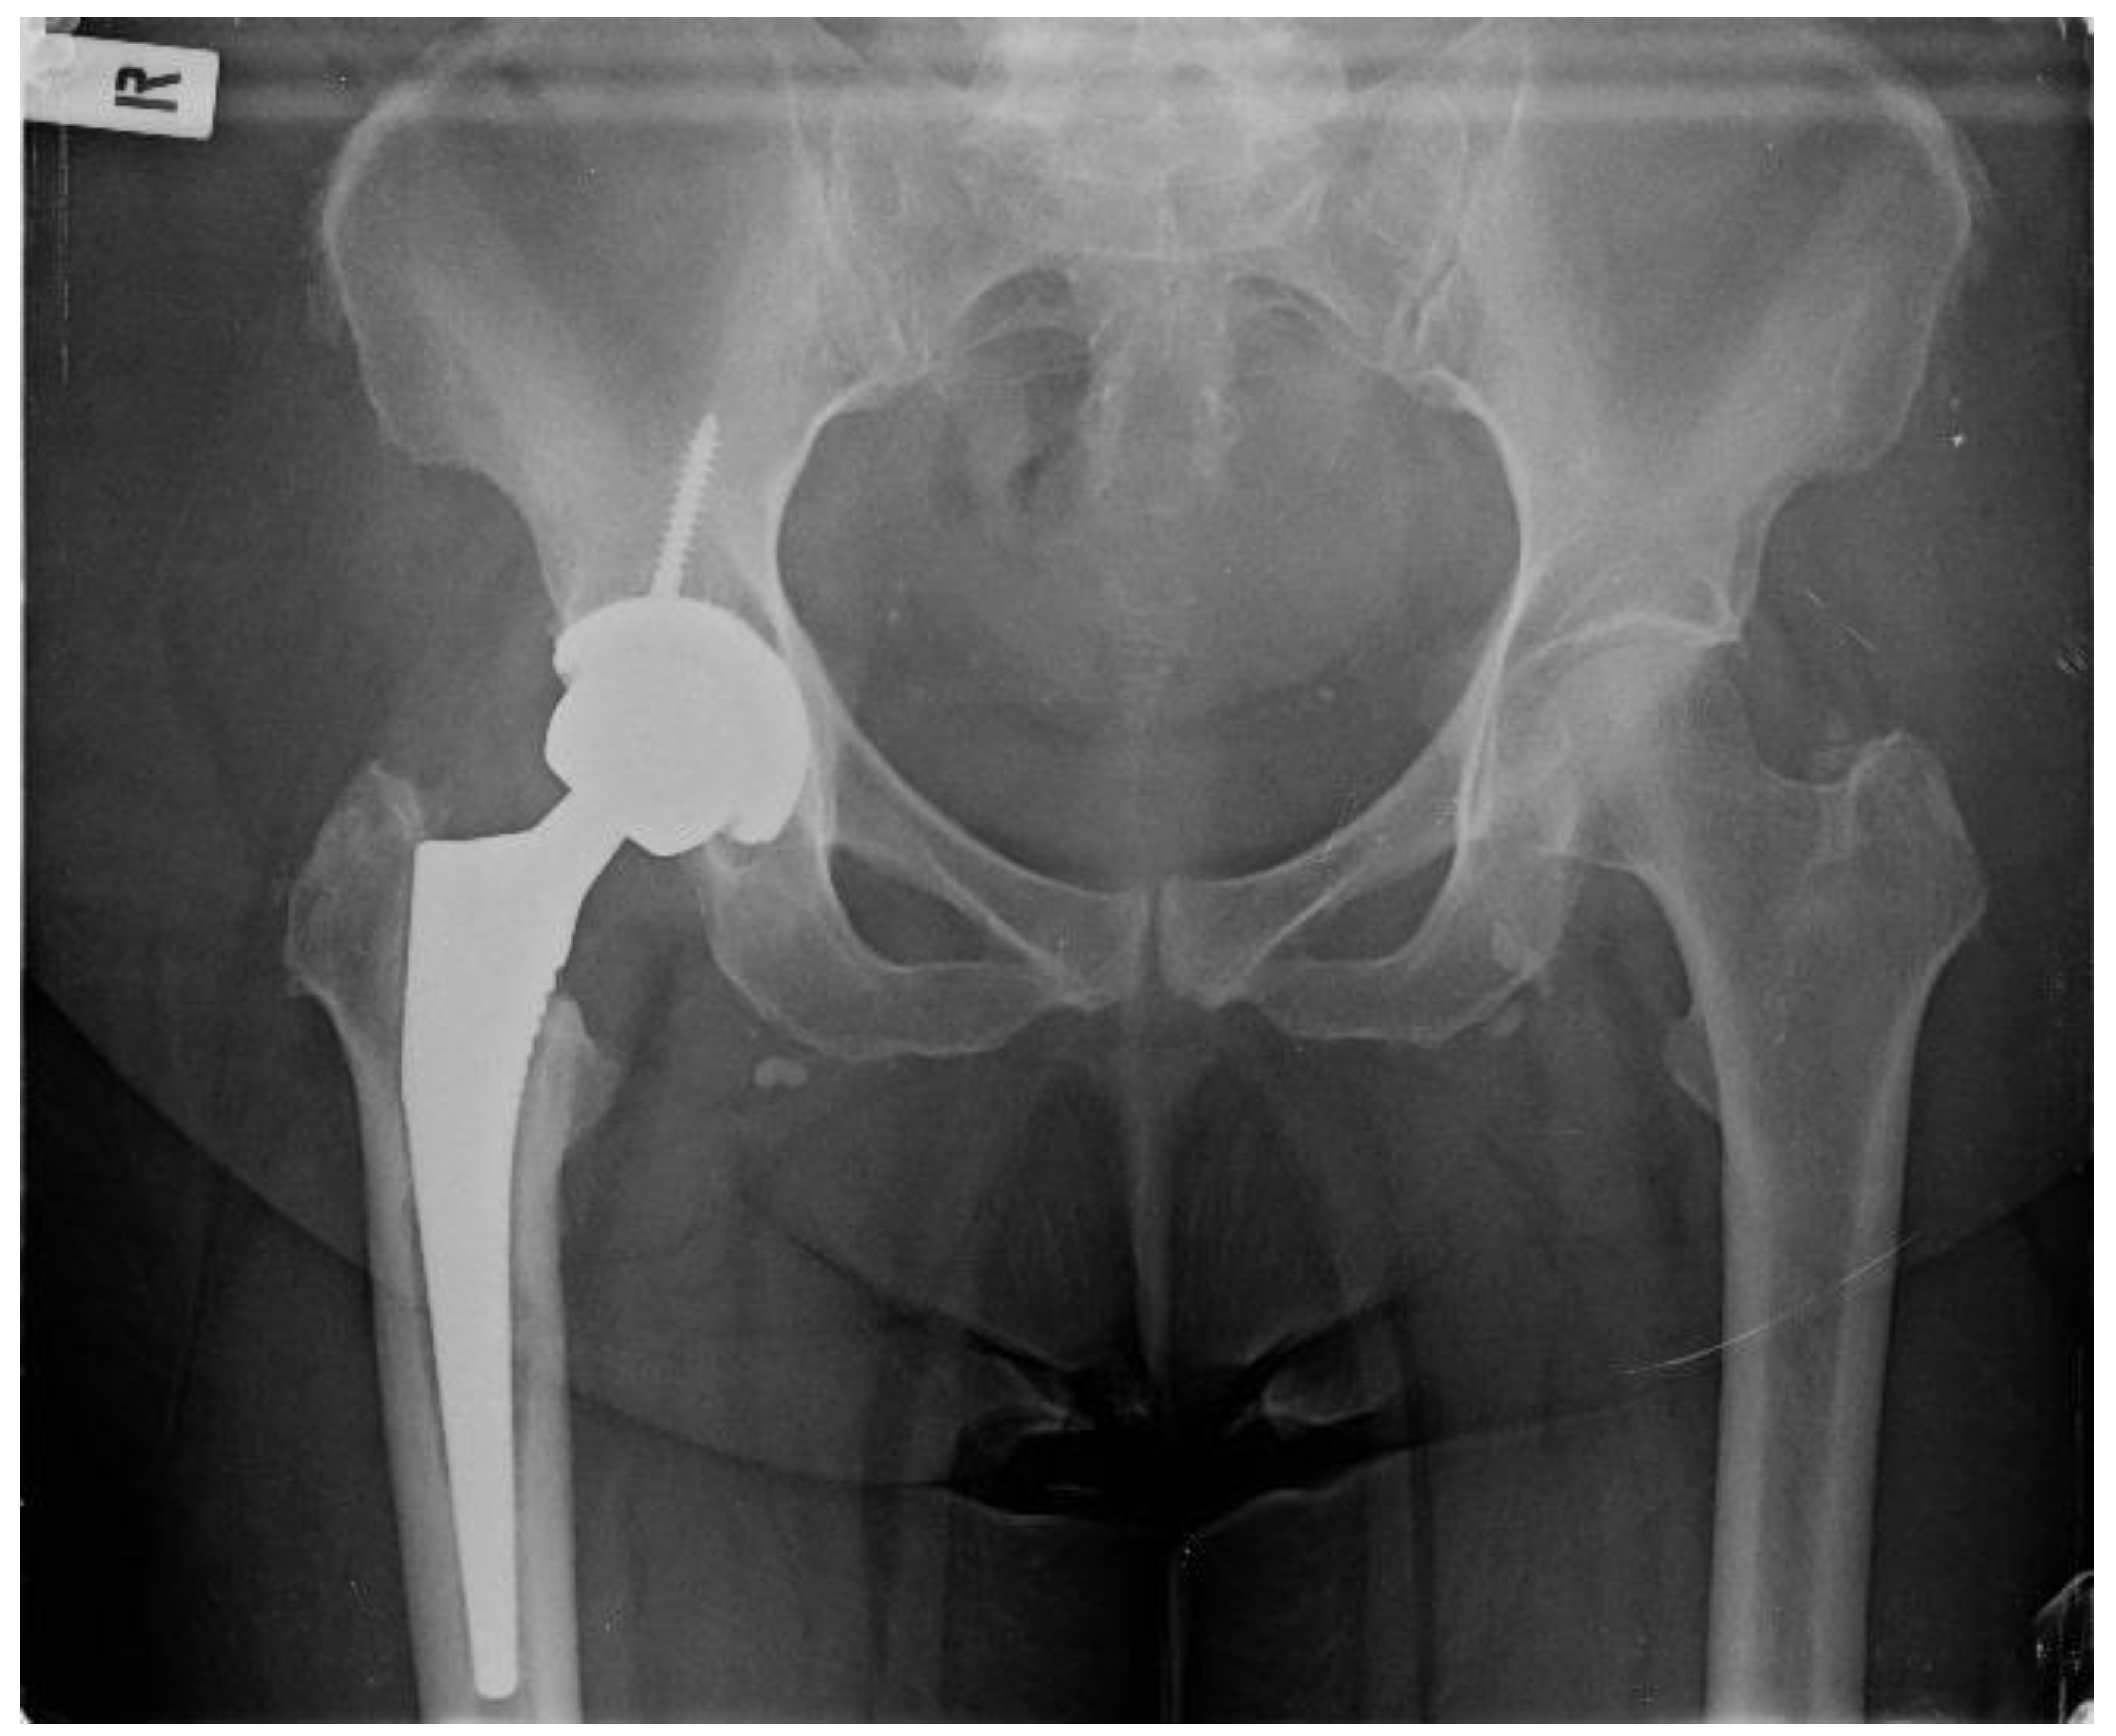

The patient presented at our clinic complaining about persistent right-hip pain for the last three years, intermittent serous fluid leakage from specific parts of the AMIS wound and baffling swelling. She has not been able to perform full weight-bearing since. Upon clinical examination, a limited range of hip motion was revealed (flexion 50 degrees, extension 10 degrees), and a sinus tract formation on the distal part of the wound was described. She was promptly admitted to our department, and a swift decision was made for absolute metalwork removal and exchange with a gentamicin-preloaded spacer after confirming that the patient had not received any antibiotics in the last six months. Concerning the lab workup, the patient`s white blood cell count (WBCs) and C-reactive protein (CRP) on admission were 11.6 × 103/μL and 7.2 mg/dL, respectively. Given that the patient might need more hip operations and a revision THA was requisite should the infection be eradicated, a conventional posterior hip approach was utilised for better and greater exposure of the hip joint and adjacent soft tissues. After punctilious washout, bone and soft tissue debridement, and complete metalwork extraction, nine (9) standard bone and soft tissue cultures were sent for analysis and culture. At the same time, a hip spacer (Spacer G, Tecres SpA, Verona, Italy) was implanted as planned (Figure 2).

Figure 2. Hip X-ray after arthroplasty removal and implantation of the spacer.